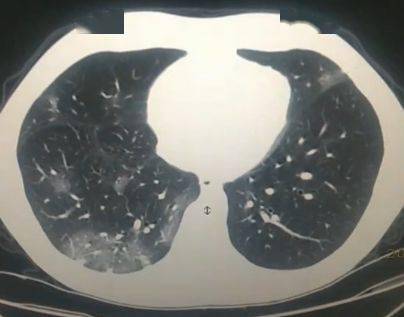

肺炎dr图片怎么看

肺炎dr图片怎么看,肺炎图片

厉害!看看如何利用dr做断层诊断新冠肺炎

动态dr 在新型冠状病毒肺炎诊疗中的应用

肺炎ct图片

新冠肺炎图片

肺炎

新冠肺炎